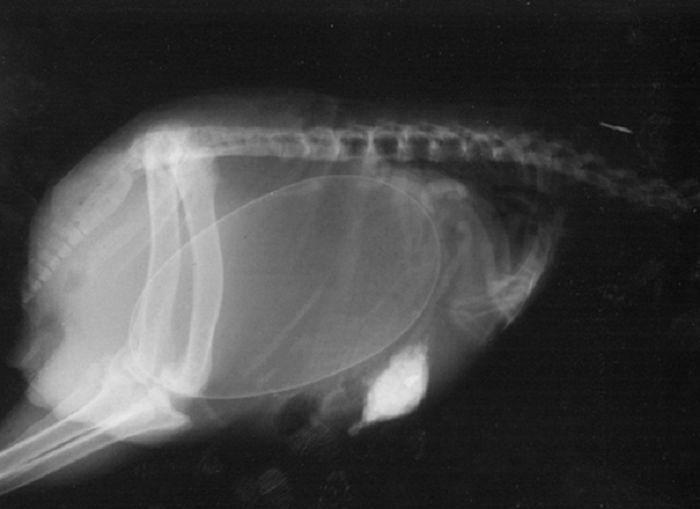

以下就是一些动物在怀孕时的X光片。

4. 猫